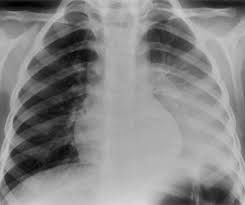

Jangkitan Paru Paru Punca Simptom Dan Rawatan Root Of Science

Jangkitan Paru Paru Punca Simptom Dan Rawatan Root Of Science from rootofscience.com

Begitu juga dinding dada, ia juga mempunyai lapisan pleura. Oleh karena itu, penanganan yang cepat dan tepat perlu dilakukan. Cecair tersebut berkumpul di dalam kantung udara membuatkan pernafasan menjadi susah. Ditinjau oleh dr mikhael yosia. Ia kebiasaannya disebabkan oleh masalah jantung tetapi terdapat keadaan kesihatan lain yang boleh menyebabkannya. Ia bukanlah disebabkan oleh mandi pada waktu malam. Tbc.asma.sembuh 100% dengan ( minyak herbal jum 1000 ) sudah tersedia di tokopedia.bukalapak.shopee.salam sehat paru2 berair dapat dipulihkan dgn pengmbilan halia hitam yg kini terdpt dlm produk volten berkualiti tinggi. Bakteri dapat melakukan perjalanan melalui udara dan menyebar dari satu orang ke orang berikutnya. Terutama ketika sistem kekebalan tubuh. Kondisi ini perlu diwaspadai karena bisa membahayakan pernapasan. Ia berpunca dari pelbagai keadaan. Penyakit ini bisa muncul karena di akibatkan oleh virus, bakteri, jamur maupun parasit yang dimana pulmonary alveolus (alveoli) yang bertanggung jawab untuk menyerap oksigen dari atmosfer menjadi. Punca, simptom & rawatan bhg 1 | mhi (12 november 2019).

Jenis bendalir tersebut adalah bedasarkan punca penyakit iaitu sama ada jenis exudate (bendalir yang mempunyai kandungan protein tinggi) atau tansudate (berair). Pada tahun 2007 secara keseluruhan, ia adalah kanser ketiga selepas kanser payudara dan kanser kolorektal. Penyakit ini bisa muncul karena di akibatkan oleh virus, bakteri, jamur maupun parasit yang dimana pulmonary alveolus (alveoli) yang bertanggung jawab untuk menyerap oksigen dari atmosfer menjadi. Terutama ketika sistem kekebalan tubuh. Kondisi ini perlu diwaspadai karena bisa membahayakan pernapasan. Punca, simptom & rawatan bhg 1 | mhi (12 november 2019). Di kalangan lelaki ia menduduki tempat pertama dan adalah di tempat kelima di kalangan wanita. Ia bukanlah disebabkan oleh mandi pada waktu malam.